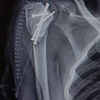

After 24 h of overnight intubation, staged posterior stabilization from C1-C3 was performed 7 days later. The patient was positioned prone on a Jackson table and the head was stabilized using a Mayfield head holder. Using a midline skin incision, C1–C3 was exposed bilaterally by exposing the C1–C2 joint and C1 lateral masses. For this, we exposed the venous plexus and cut the C2 nerve roots B/L. Bleeding from the vascular plexus was controlled using a combination of bipolar cautery, hemostatic matrix – Floseal; Baxter Healthcare Corporation Fremont, CA 94555, USA) and, gel foam. Using the navigation, it was noted that the pedicle on the right side of C2 was very narrow and precluded the placement of a pedicle screw, hence, a pars screw was preferred. A pilot hole was created with the aid of navigation, followed by insertion of the probes, taps, and screws according to the measured lengths. Finally, rods were inserted and C1–C3 stabilization was performed (Fig. 7). Bone grafts (allografts with demineralized bone matrix – Grafton DBM; Osteotech, Eatontown, New Jersey) were placed on the lateral gutters and no decompression was performed.